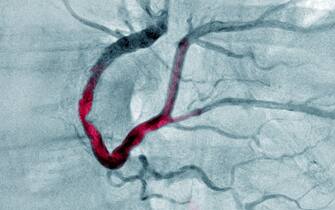

MALATTIA TROMBOTICA

• E per prevenire più efficacemente la malattia trombotica? "Un'altra importante quota di rischio residuo - evidenzia lo specialista - è legata ad una insufficiente protezione da infarto e morte improvvisa per la formazione di trombi all'interno delle arterie. Finora ci siamo difesi da questo rischio con una terapia anti-trombotica molto nota, l'aspirina

• E ancora: "Ma anche qui forse possiamo fare di meglio nel contrastare questo rischio con nuovi farmaci antipiastrinici e anticoagulanti; tra i primi, anche farmaci già in uso da tempo come il ticagrelor, che potrebbe essere utilizzato come una 'super-aspirina'; tra i secondi, molto interesse sta generando il prossimo arrivo di nuovi anticoagulanti orali, gli inibitori del fattore XI"